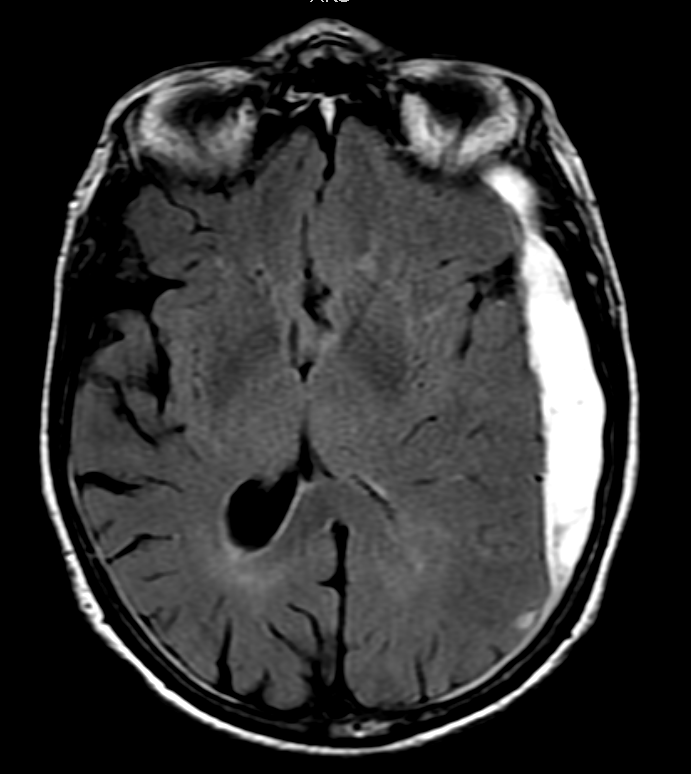

Subdural hematomas are collections of blood between the brain’s tough dural covering and thin arachnoid covering. The most common cause is tearing of venous structures, and it can be caused by minor trauma. Patient’s on anticoagulants, thrombocytopenia or significant cerebral atrophy are at higher risk.

Clues to the presence of subdural hemmorhages include:

- No extension into the sulci (as would be seen in subarachnoid bleeding)

- Concave shape, like a crescent

- Not typically associated with skull fractures, unlike epidural hematomas

- Typically slowly expanding